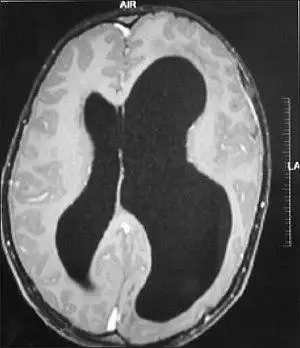

Left-sided hemimegalencephaly

Hemimegalencephaly

Hemimegalencephaly is an extremely rare form of macrocephaly and is characterized by uneven development of brain hemispheres (one-half of brain is larger than other).[7] The syndrome can be presented by itself or in association with phakomatosis or hemigigantism. Additionally, hemimegalencephaly will frequently cause severe epilepsy, focal neuro-logical deficits, macrocrania, and mild to severe mental retardation.[8]